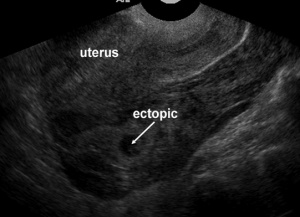

Ectopic pregnancy

- Implantation of blastocyst outside of endometrium

- Occur in fallopian tubes, cervix, ovaries, peritoneal cavity, or scar of prior uterine surgery

- Most definitive sonographic sign is gestational sac with yolk sac, embryo, or fetal heart beat outside of the endometrium

- Tubal ring

- Echogenic thick-walled anechoic sac visualized between uterus and ovary (separate from ovary when pressure applied to fallopian tube with probe)